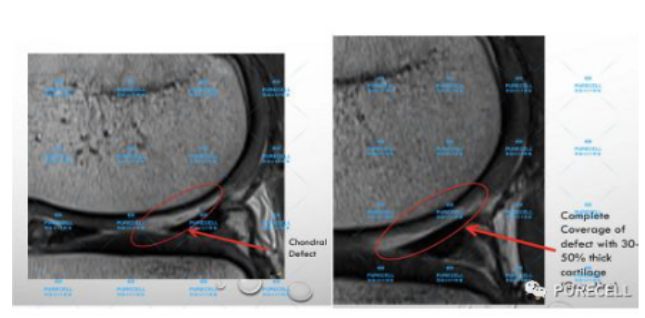

PURECELL首席科學家以及運動醫療專家已經驗證了UCF對膝關節修復的有效性,上圖是UCF軟骨及半月板修復前後影像對比

PURECELL金牌資質醫生Dr. Ian Chinse說"UCF膝關節修復的主要原理是通過UCF成分改善膝關節內環境,有效激活膝關節內沉睡的干細胞進行靶向修復。"

UCF膝關節修復一經面世,已經為成百上千的運動損傷及老年退行性病變的客人帶來意想不到的修復效果,滿意度回饋達99%以上。不開刀,不手術,微創、無痛、便利,不會造成二次損傷,是迄今為止,最理想、最革新的膝關節修復科技。